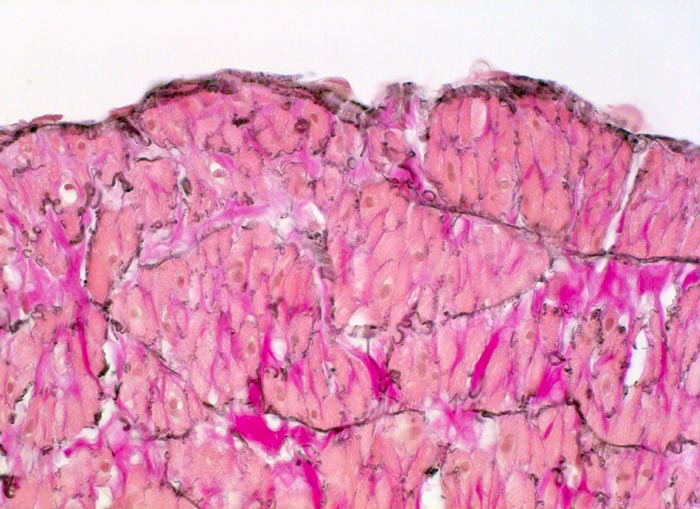

normale Venenwand: Endothel

Normalbefund

Vene

Kardiovaskuläres System

Flache

Endothelzellen der Intima grenzen unmittelbar an die glatte Muskulatur durchsetzt von elastischen Fasern der Media.

Im Gegensatz zu den Arterien ist die Intima (Endothel und subendotheliales Bindegewebe) der Vene sehr dünn.

Histologie

400